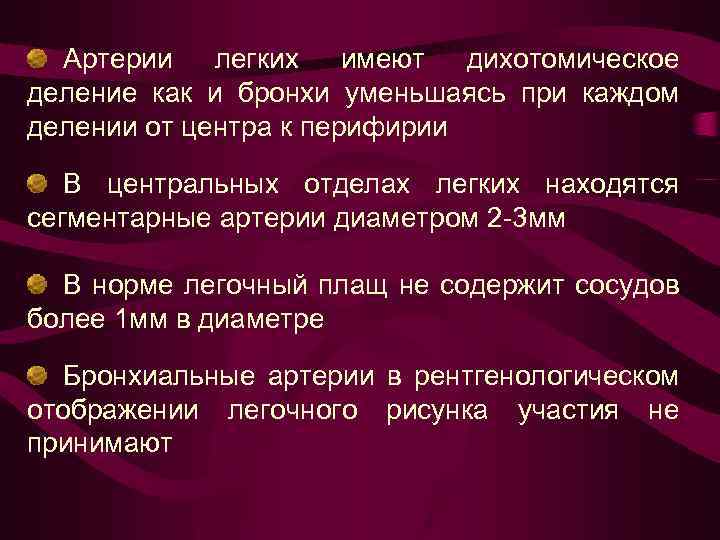

Артерии легких имеют дихотомическое деление как и бронхи уменьшаясь при каждом делении от центра к перифирии В центральных отделах легких находятся сегментарные артерии диаметром 2 -3 мм В норме легочный плащ не содержит сосудов более 1 мм в диаметре Бронхиальные артерии в рентгенологическом отображении легочного рисунка участия не принимают

Артерии легких имеют дихотомическое деление как и бронхи уменьшаясь при каждом делении от центра к перифирии В центральных отделах легких находятся сегментарные артерии диаметром 2 -3 мм В норме легочный плащ не содержит сосудов более 1 мм в диаметре Бронхиальные артерии в рентгенологическом отображении легочного рисунка участия не принимают